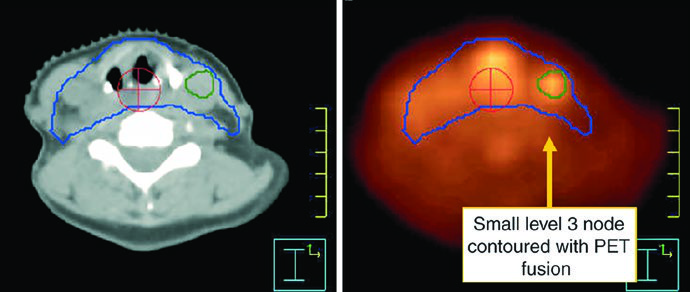

Contrast-enhanced MRI helps define locoregional extent, and the chapter calls out one practical exclusion criterion from larynx preservation trials: more than 1 cm of base of tongue invasion was not allowed in RTOG 91-11. PET/CT is then used to improve nodal detection and to look for metastatic disease.

The GTV should be built from laryngoscopy, CT, MRI, and PET together. Positive neck nodes include those with central necrosis, extracapsular extension, or short-axis diameter greater than 1 cm. Borderline nodes with FDG avidity should be treated as involved disease. Small bean-shaped nodes with a fatty hilum are more likely benign, but enlarged retropharyngeal nodes should be considered positive even when they are small because that pattern is unusual enough to matter.

| CTV 54b | Levels II-IV of the uninvolved neck. In the node-negative neck, the superior border of level II stops where the posterior belly of the digastric crosses the internal jugular vein, or at the caudal edge of the lateral process of C1. Levels IB and V are not included unless there is gross disease at those levels. Retropharyngeal nodes may be covered at physician discretion on the side of bulky adenopathy because of retrograde flow. Level VII coverage is recommended for subglottic extension or hypopharyngeal involvement. |

Levels IB and V are not elective by default and are only included when gross disease is present there. Retropharyngeal nodes may be covered on the side of bulky adenopathy at physician discretion. Level VII is recommended for subglottic extension or hypopharyngeal involvement. That is one of the most useful parts of the chapter because it turns abstract spread patterns into concrete cranial and caudal borders.